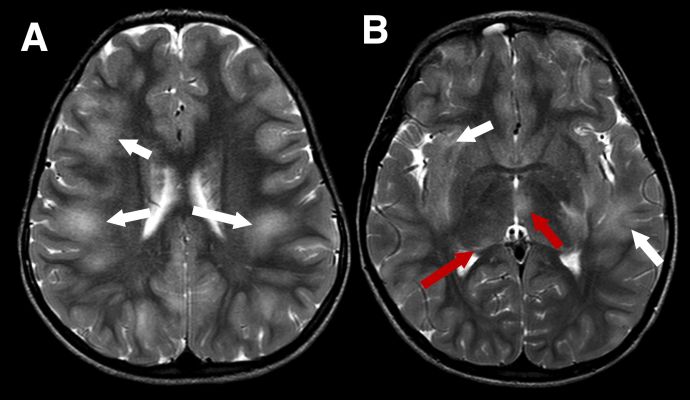

MRI findings depend on presenting phenotype e.g. ADEM vs ON, although there is some crossover. Due to the aforementioned predilection for MOGAD to present as ADEM in younger children the MRI features are inherently different to those seen in adults. MRI features of ADEM are typically bilateral deep white and grey matter lesions which are T2 hyperintense large (>2cm) in size and poorly demarcated (Figure 1). However, MRI findings in pediatric ADEM can demonstrate a “leukodystrophy-like” pattern which includes predominantly confluent and bilateral white matter changes and is associated with a poorer outcome (Figure 2).[18]

Figure 1 Typical imaging appearances in a child with acute disseminated encephalomyelitis (ADEM) MOGAD phenotype in the acute phase. Axial T2-weighted images show large, extensive, ill defined areas of high signal throughout the subcortical white matter and left temporal stem (A and B, white arrows). The thalami are also involved more inferiorly (B, red arrows)